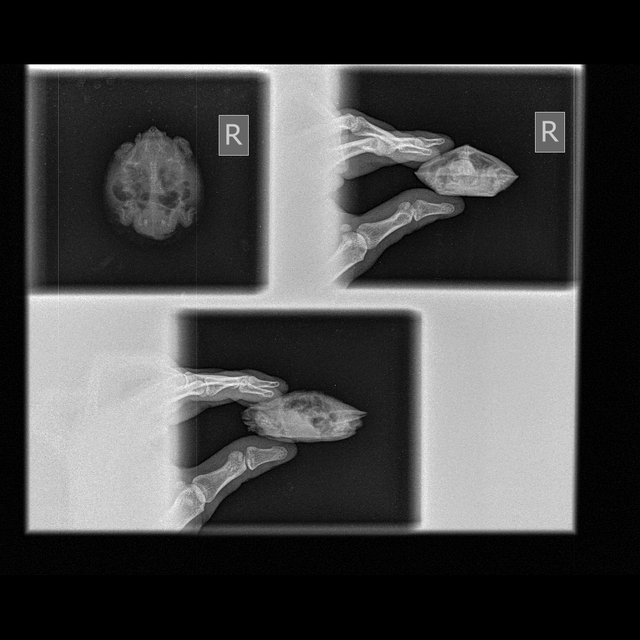

Консультанты moth Ваше имя: Мария Локация: Москва Опубликовано: 22 сентября 2025 Консультанты Опубликовано: 22 сентября 2025 @Paradox если сможете - нужны две проекции 1 и 3

Paradox Ваше имя: Роман Локация: Кыргызстан, Бишкек Опубликовано: 23 сентября 2025 Автор Опубликовано: 23 сентября 2025 @moth Сделали снимок

Консультанты moth Ваше имя: Мария Локация: Москва Опубликовано: 23 сентября 2025 Консультанты Опубликовано: 23 сентября 2025 @Paradox жкт очень сильно раздуло она вообще активная? плавает или в основном на берегу сидит?